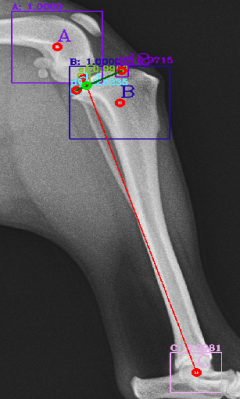

Most of the source dataset of over a thousand unique knee radiographs were distorted, had poor patient positioning, or were otherwise unfit for annotating. 250 of the original images were of sufficient quality to contribute to this effort. These images were set to have 6 different classes for training purposes, as mentioned and shown in Fig. 4. These were then trained using YOLOv3 [10] and the results of the predicted annotations are shown in Table I. From these predictions the centroids were extracted, which is then used to plot the FTL and MTPL. Then using the method mentioned in Section II, TPA is calculated. Examples of images, the region of interests detection and their respective TPA determination is shown in Fig. 6 and Table I:

| Image | YOLOv3 | YOLOv4-1 | YOLOv4-2 | YOLOv4-3 |

|---|---|---|---|---|

| 6(a) | 20.537° | 22.67° | 24.8° | 22.9° |

| 6(b) | 17.354° | 17.62° | 18.7° | 16.22° |

| 6(c) | 19.473° | 19.53° | 20.03° | 18.24° |

| 6(d) | 23.369° | 27.37° | 29.03° | 25.8° |

| 6(e) | 18.435° | 15.5° | 17.65° | 16.8° |

| 6(f) | 19.699° | 18.24° | 20.22° | 18.59° |

For comparison purposes the radiographs have been tested with YOLOv3, original YOLOv4 [12] and custom modifications of the YOLOv4 by changing the activation functions and the results are shown in Table II. The original version of YOLOv4 (addressed as YOLOv4-1 in Table II) combined the Mish, Linear and Leaky activation functions, the versions YOLOv4-2 and YOLOv4-3 used for the purpose of testing in this paper have combinations of Mish, Linear, Swish and Mish, Linear and Relu activation functions respectively. Similarly, comparison of the results that did not fall under the presumed normal range shown in Fig. 9, for the algorithm, are shown with variations in activation function in Table III. It can be seen here that these images, are giving TPA predictions similar to the original YOLOv3, i.e. outside of presumed range.